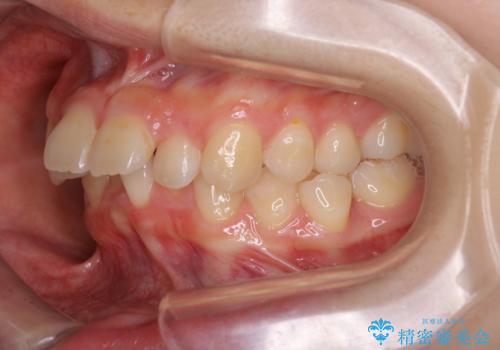

- 前歯が出ていることを主訴に来院されました。

下顎前歯が1本欠損していることもあり、前突はある程度残ることを説明し、インビザラインにて治療を行いました。

今回は抜歯矯正ではなく歯列弓の拡大とIPR、遠心移動を行って配列することができました。

口元も改善し患者さんには喜んでいただけました。

下顎前歯が1本少ないため、上下の正中は合いません。